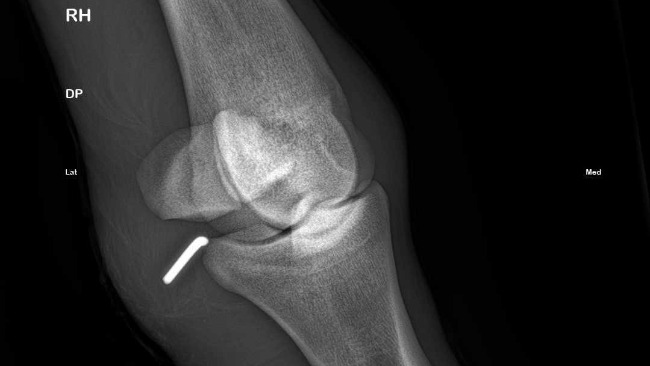

Około godziny 23:00 dotarliśmy na miejsce, gdzie zrobiono Rokiemu zdjęcia RTG nóżki i wtedy nastąpił szok: obce ciało (prawdopodobnie kawałek drutu) wbity w staw. Jak on się tam dostał? Nie mamy pojęcia. Decyzja: Młody zostaje w klinice, rano konsultacja z jej szefem, badanie stopnia zakażenia rany i tel do nas.